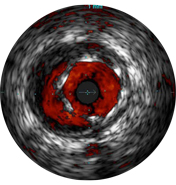

Malapposition is identified by blood behind the stent struts. ChromaFlo imaging colors blood flow red for easy recognition of malapposition and other lumen features.